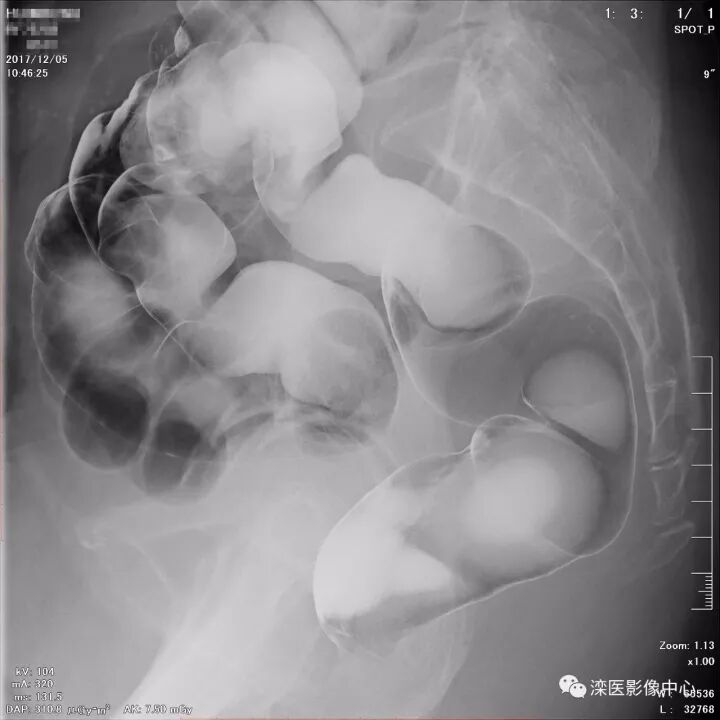

下面请您审阅近期我院影像科开展下消化道双对比造影检查的图像:

(以上图像是对结肠脾曲、横结肠、结肠肝曲的显示)